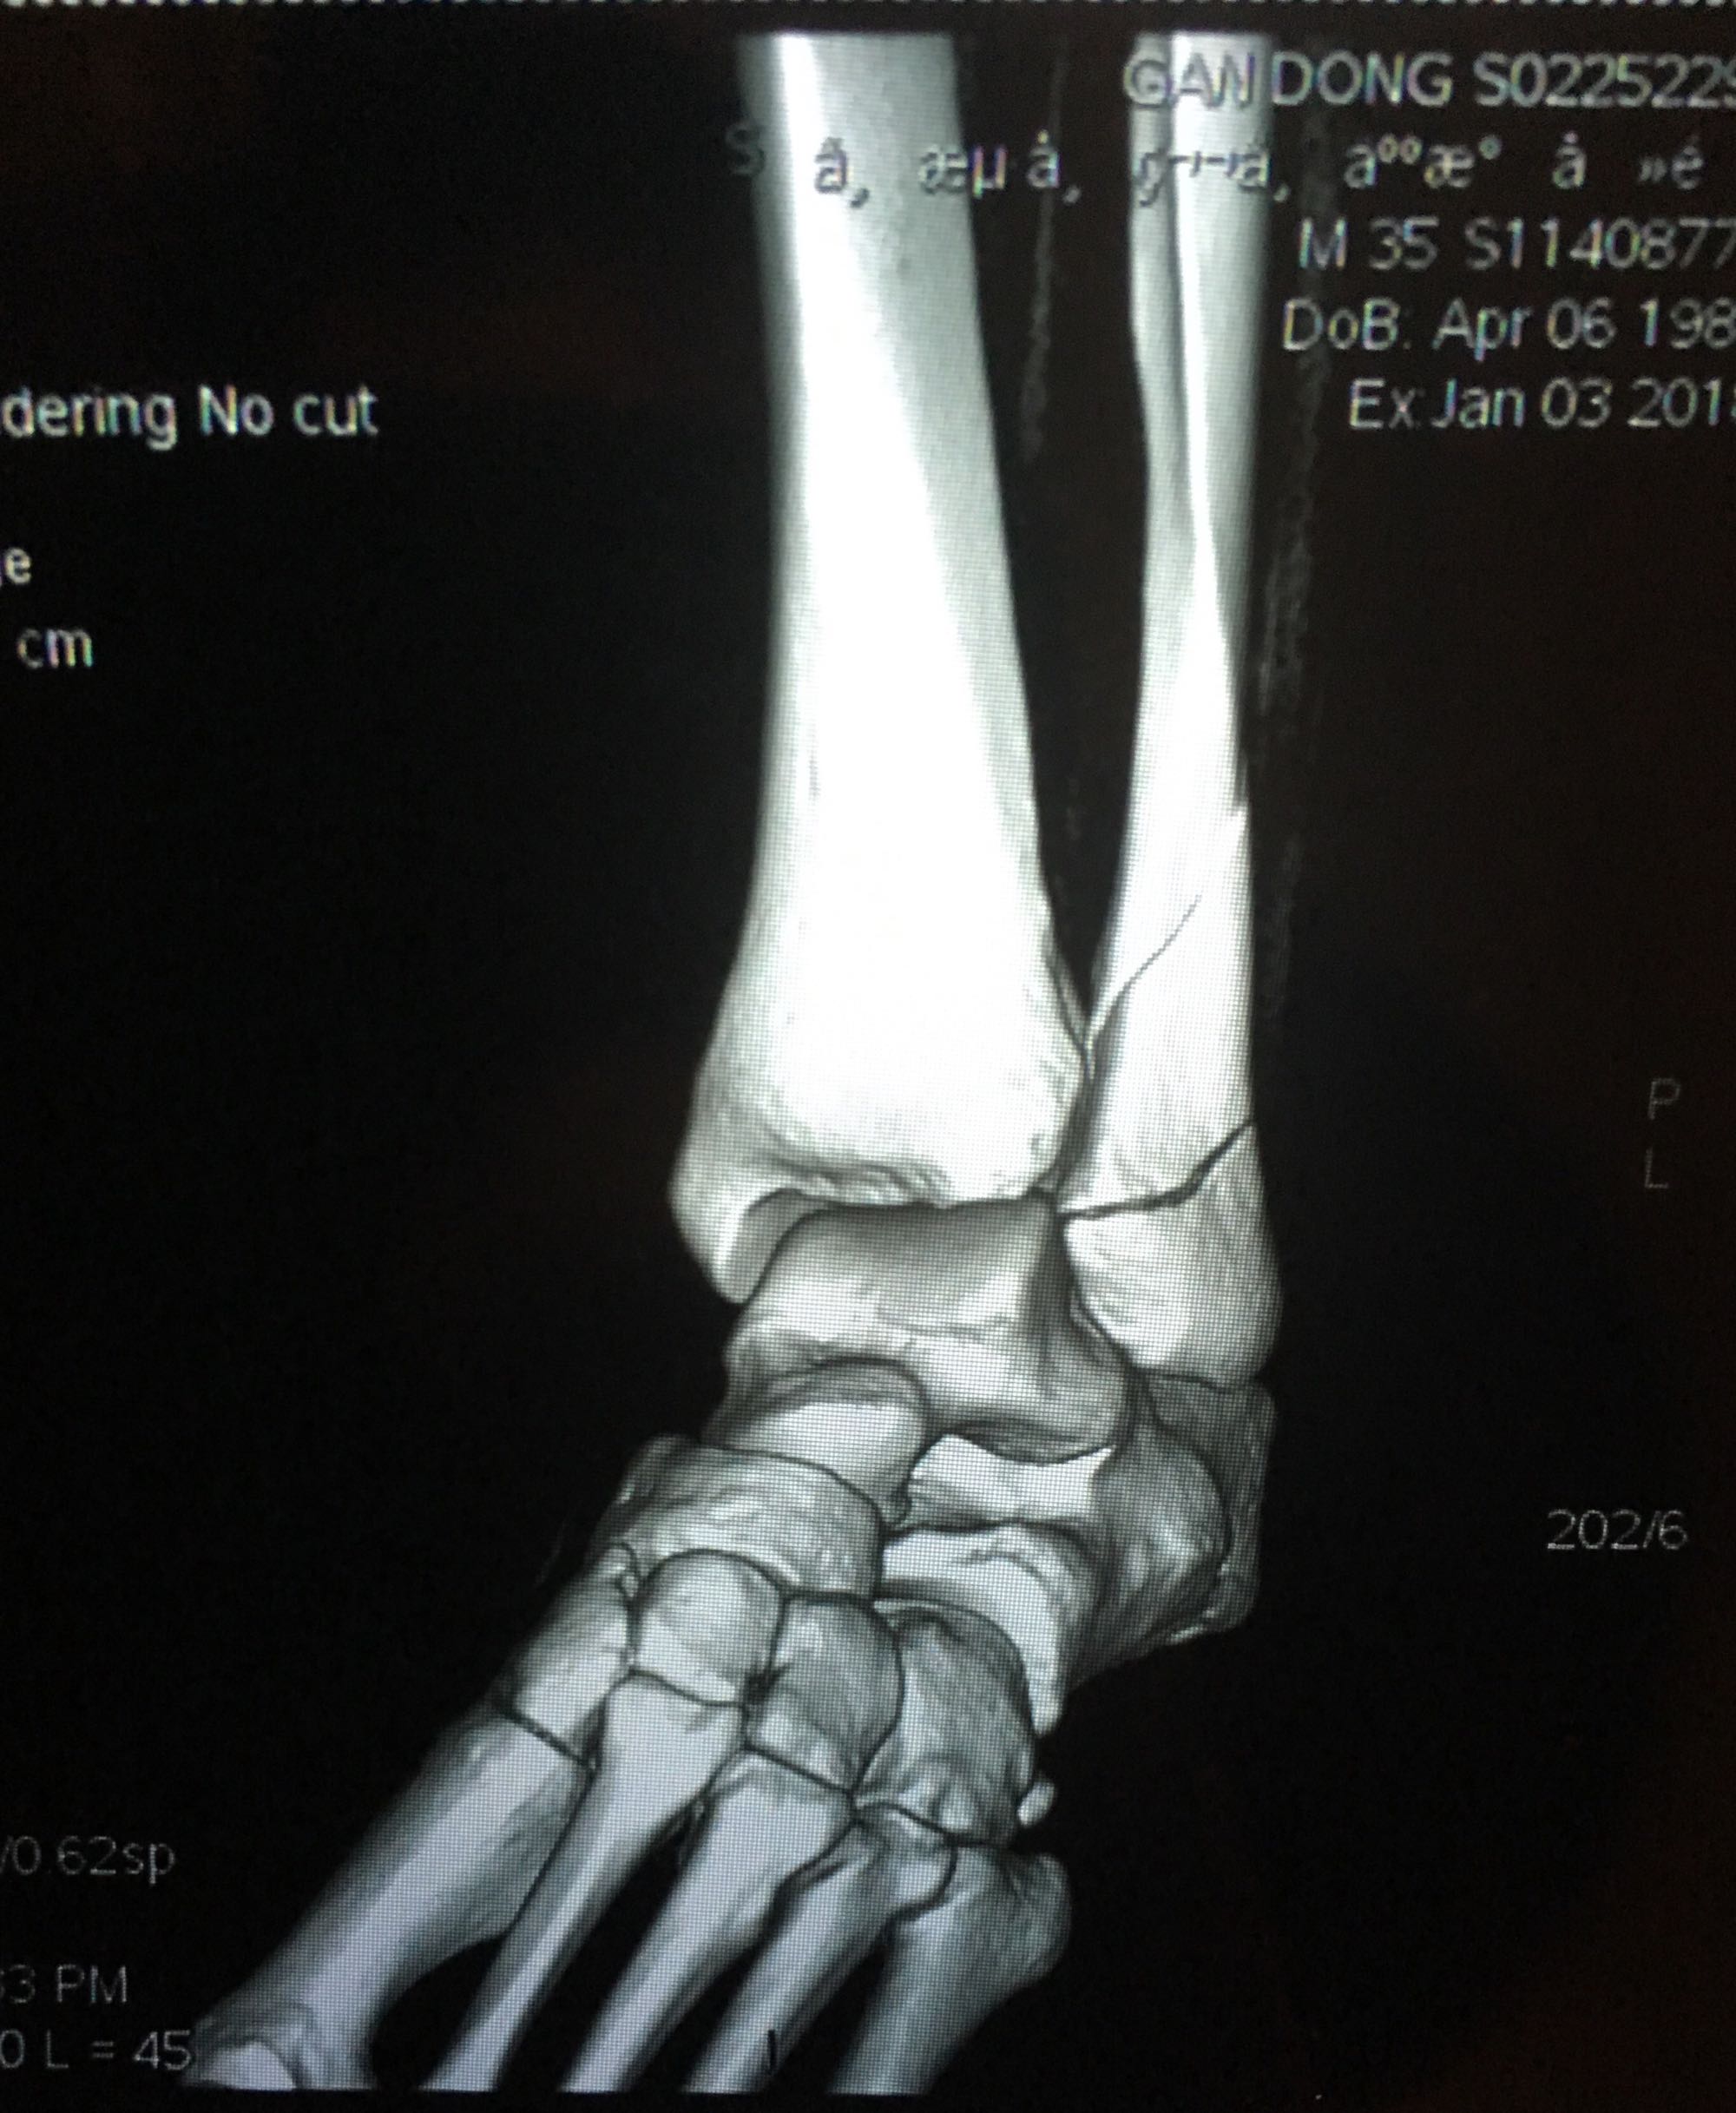

腓骨靠近踝关节处骨折,已经第七天了,西医建议手术,中医说不手

三踝骨折吧

腓骨靠近踝关节处骨折,已经第七天了,西医建议手术,中医说不手术固定好也可,迷茫中……

这个不是近关节骨折,这个是关节内骨折,关节腔肯定伤到了。手术并正确康复训练的话后遗症小,保守治疗后期康复很痛苦,同时高风险有后遗症